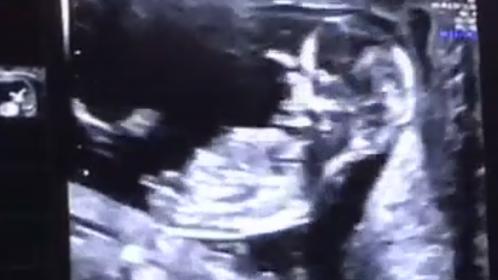

I'm going to guess boy from these :)

Definitely boy from the recent pics [emoji170]

Last pic is that a perfect nub shot?? Lol im reviewing a video she send me & im going slow motion to catch the perect nub shot & i think this is it!